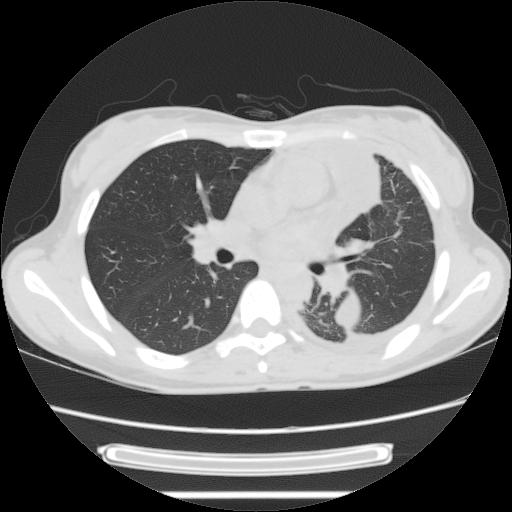

女,29岁,胸部不适,在外院胸片提示胸腔积液,到我院ct检查。

纵膈窗